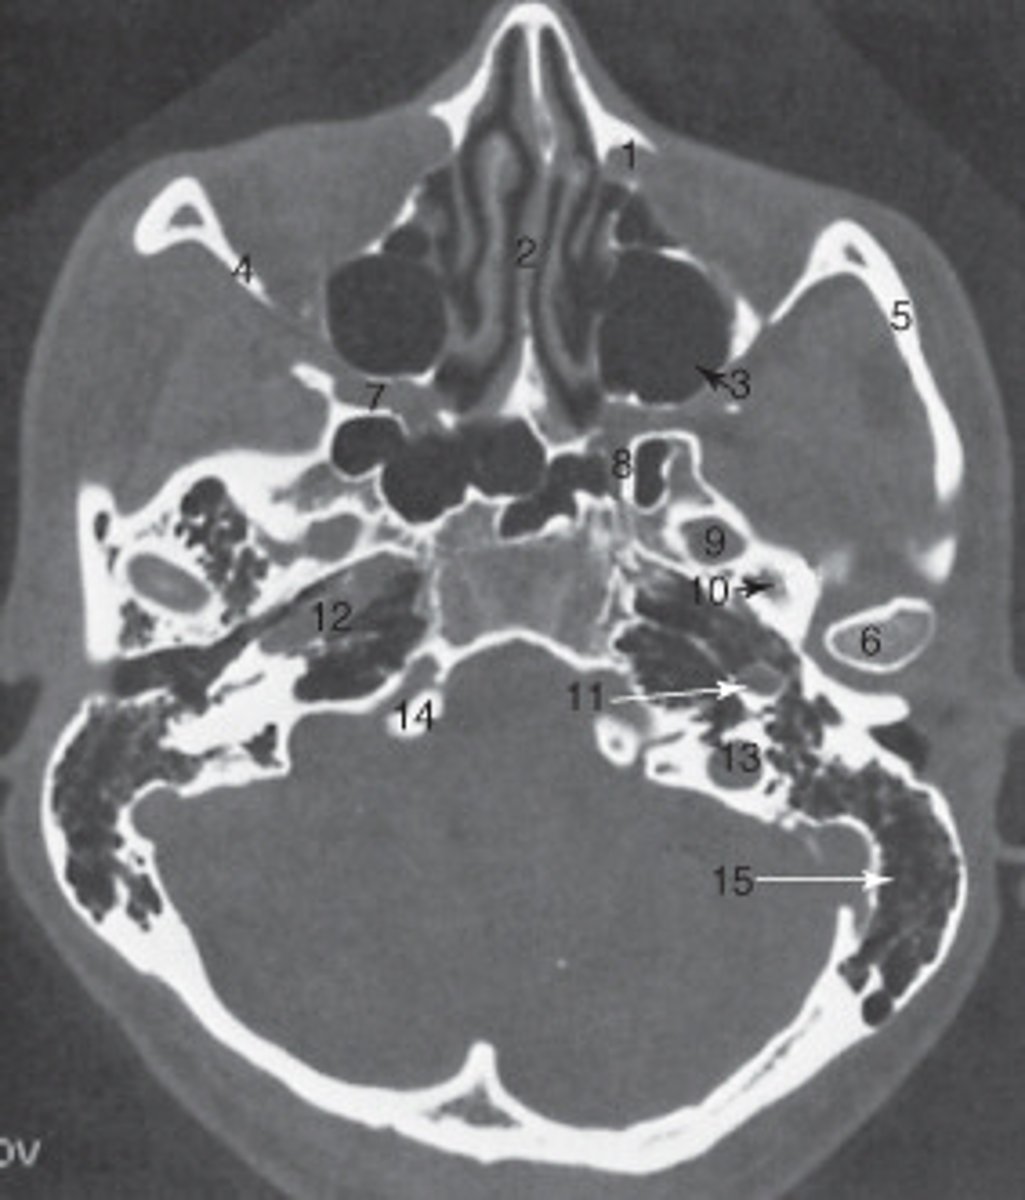

the mastoid air cells are labeled:

<p>the mastoid air cells are labeled:</p>

manidubular condyle

the structure labeled 6 is the:

zygomatic arch

the structure labeled 5 is the:

The sphenoid sinus is labeled:

<p>The sphenoid sinus is labeled:</p>

The internal jugular vein is labeled:

<p>The internal jugular vein is labeled:</p>

10

the parotid gland is labeled:

internal carotid artery

the structure labeled as 8 is the: